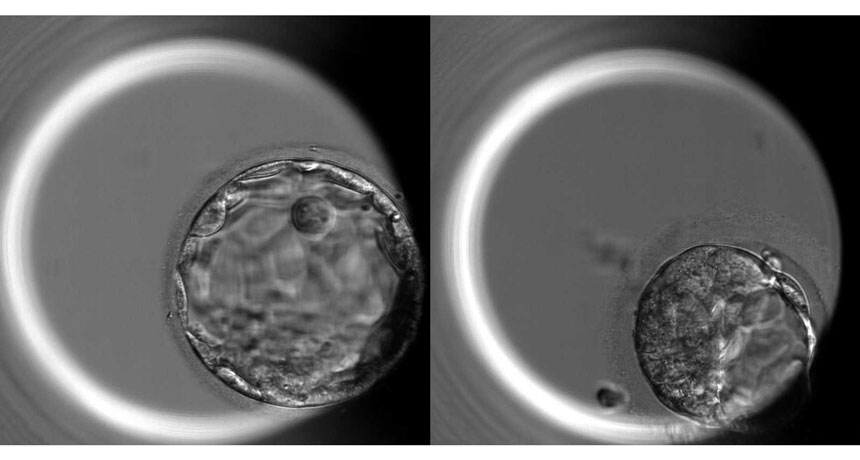

EMBRYO, INTERRUPTED  A 5-day-old human embryo is usually composed of about 200 cells in a hollow ball configuration called a blastocyst (left). Embryos edited to remove the OCT4 gene (right) fail to make normal blastocysts.

In the experiment, human embryos lacking OCT4 had difficulty reaching the blastocyst stage: Only 19 percent of edited embryos formed blastocysts, while 47 percent of unedited embryos did. Blastocysts are balls of about 200 cells that form about five or six days after fertilization. The ball’s outer layer of cells gives rise to the placenta. Inside the blastocyst, one type of embryonic stem cells will become the yolk sac. Another kind, about 20 cells known as epiblast progenitor cells, will give rise to all the cells in the body.